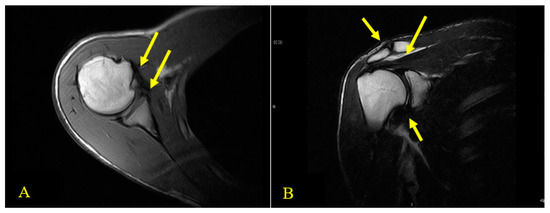

2.2. Physical Examination and the Physical Therapist’s Diagnosis